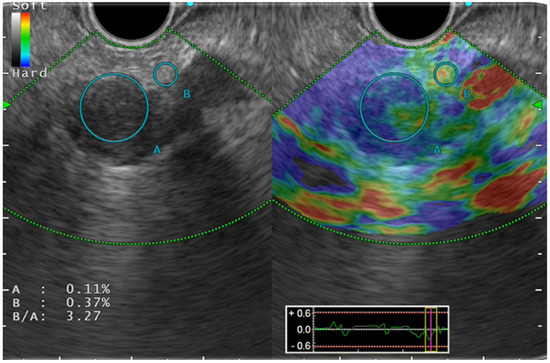

Color pattern diagnosis is the qualitative evaluation method used for SE (Figure 1). Generally speaking, color pattern diagnosis is used for major color tones of tumors (blue, hard; red, soft), and for heterogeneous or homogeneous color tones. Giovannini et al. first reported the elastic score: a color pattern diagnosis. The elastic score, color pattern, and heterogeneity of distribution of the elastography were classified into five types [13]. The quantitative evaluation methods are classified into SR and SH. The former, SR, is the ratio of the target lesion strain to the peripheral tissue strain [14]. The latter, SH, evaluates a grayscale histogram created by converting an elastography image into a gray scale of 256 tones, thereby yielding feature values [15]. The mean value, which is one of the feature values, is reportedly correlated with the degree of pathological pancreatic fibrosis. The SH results, used along with neural network analysis (NN), are particularly valuable for differential diagnosis of pancreatic cancer from pancreatic inflammatory masses [16].

Figure 1.

Strain elastography.

In fact, CP has a higher degree of hardness than a normal pancreas (Figure 2). Generally speaking, CP appear as blue and heterogeneous on EUS-EG as the disease progresses, which correlates with the Rosemont classification [11,15,20]. Kim et al. have described a mean SR of 3.78 ± 1.35 for a normal pancreas and 8.21 ± 5.16 for CP. Using a cut-off value of 5.62, the sensitivity, specificity, and accuracy of SR for detecting CP were, respectively, 72%, 75%, and 75% [21]. Several published reports have described the usefulness of EUS-EG for CP (Table 1).

Figure 2.

Endosonography (EUS) elastography in chronic pancreatitis.